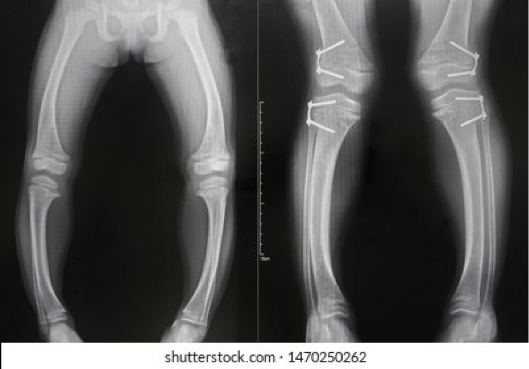

vara; medial

in blount’s disease, there is tibia _______ and (medial or lateral) growth plate dysfunction